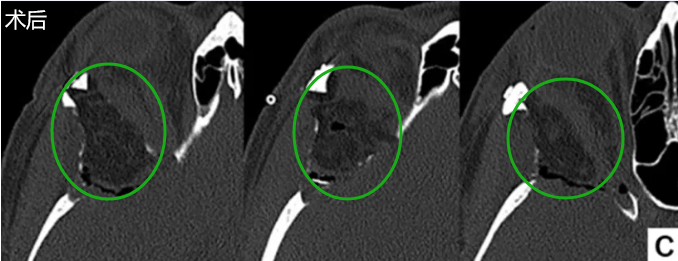

术前轴位计算机断层扫描,显示反应性骨质增生及肿瘤累及骨骼的范围(图E)。术后MRI(图F)显示眼球突出显著改善(眼球突出指数=1.11)。